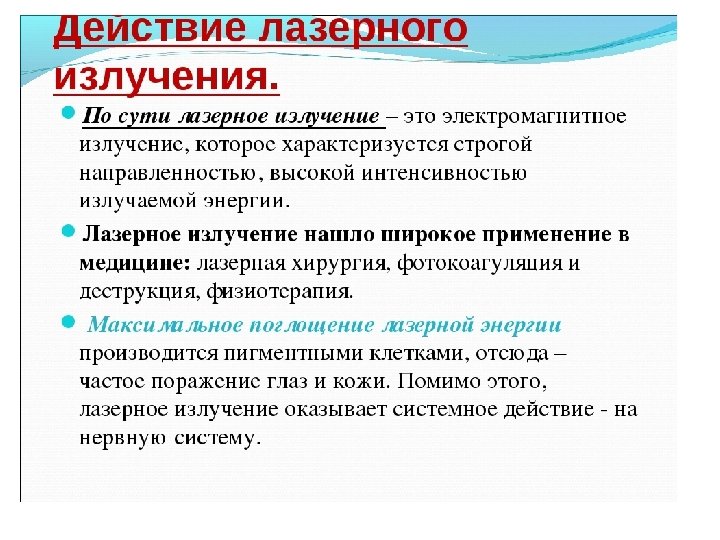

Классификация профессиональных заболеваний Промышленных аэрозолей (пневмокониозы; пылевой бронхит; профессиональная бронхиальная астма; экзогенный аллергический альвеолит, бериллиоз и др. ) Физических факторов производственной среды (вибрационная болезнь; заболевания, связанные с воздействием контактного ультразвука – вегетативно сенсорная полиневропатия; нейросенсорная тугоухость от воздействия шума; заболевания, связанные с воздействием электромагнитных излучений и лазерного излучения; ионизирующего излучения лучевая болезнь; заболевания, связанные с изменением атмосферного давления – декомпрессионная болезнь; заболевания, возникающие при неблагоприятных метеорологических условиях – перегрев, облитерирующий эндартериит, вегетативно сенсорная полиневропатия). Химических факторов (острые и хронические интоксикации, а также их последствия, протекающие с изолированным или сочетанным поражением различных органов и систем). Перенапряжением отдельных органов и систем организма (невриты, радикулополиневропатии, шейно плечевые радикулопатии, вегетомиофасциты; заболевания опорно двигательного аппарата – хронические тендовагиниты, стенозирующие лигаментозы, бурситы, эпикондилозы плеча, деформирующие остеоартрозы; координаторные неврозы – писчий ангиоспазм, другие формы функциональных дискинезий; заболевания голосового аппарата – фонастения; органа зрения – астенопия и миопия; нервно психические перегрузки – невроз у работников, обслуживающих душевнобольных пациентов). Биологических факторов (инфекционные и паразитарные заболевания – туберкулез, бруцеллез, сап, сибирская язва, дисбактериоз, кандидамикоз кожи и слизистых оболочек, висцеральный кандидоз, профессиональные аллергические заболевания –бронхиальная астма, аллергический ринит, дерматит, экзема, конъюнктивит). Вне этиологической группировки в классификацию профессиональных заболеваний включены: Профессиональные онкологические заболевания (опухоли кожи, мочевого пузыря, печени, дыхательной системы и др. ) Профессиональные заболевания кожи.

Классификация профессиональных заболеваний Промышленных аэрозолей (пневмокониозы; пылевой бронхит; профессиональная бронхиальная астма; экзогенный аллергический альвеолит, бериллиоз и др. ) Физических факторов производственной среды (вибрационная болезнь; заболевания, связанные с воздействием контактного ультразвука – вегетативно сенсорная полиневропатия; нейросенсорная тугоухость от воздействия шума; заболевания, связанные с воздействием электромагнитных излучений и лазерного излучения; ионизирующего излучения лучевая болезнь; заболевания, связанные с изменением атмосферного давления – декомпрессионная болезнь; заболевания, возникающие при неблагоприятных метеорологических условиях – перегрев, облитерирующий эндартериит, вегетативно сенсорная полиневропатия). Химических факторов (острые и хронические интоксикации, а также их последствия, протекающие с изолированным или сочетанным поражением различных органов и систем). Перенапряжением отдельных органов и систем организма (невриты, радикулополиневропатии, шейно плечевые радикулопатии, вегетомиофасциты; заболевания опорно двигательного аппарата – хронические тендовагиниты, стенозирующие лигаментозы, бурситы, эпикондилозы плеча, деформирующие остеоартрозы; координаторные неврозы – писчий ангиоспазм, другие формы функциональных дискинезий; заболевания голосового аппарата – фонастения; органа зрения – астенопия и миопия; нервно психические перегрузки – невроз у работников, обслуживающих душевнобольных пациентов). Биологических факторов (инфекционные и паразитарные заболевания – туберкулез, бруцеллез, сап, сибирская язва, дисбактериоз, кандидамикоз кожи и слизистых оболочек, висцеральный кандидоз, профессиональные аллергические заболевания –бронхиальная астма, аллергический ринит, дерматит, экзема, конъюнктивит). Вне этиологической группировки в классификацию профессиональных заболеваний включены: Профессиональные онкологические заболевания (опухоли кожи, мочевого пузыря, печени, дыхательной системы и др. ) Профессиональные заболевания кожи.